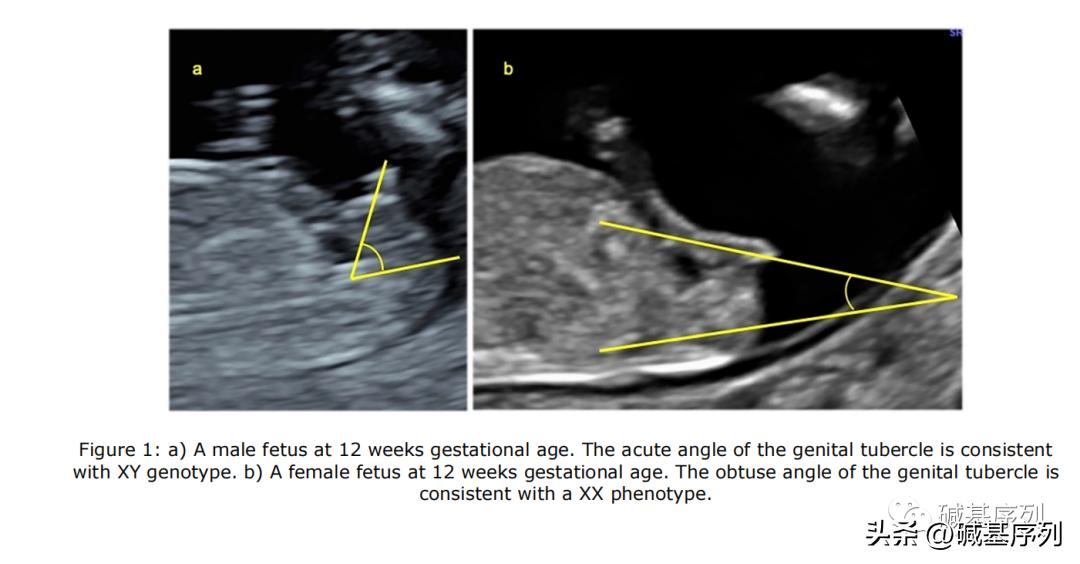

XX和XY基因型胎儿的超声表现

产前无创筛查(non-invasive prenatal testing, NIPT)发现性染色体异常。NIPT对性染色体非整倍体的阳性预测值(positive predictive value, PPV)约为32% ~ 57.6%。

在 Richardson等(2017) 研究中,NIPT提示的胎儿性别与孕期B超显示的胎儿性别之间不一致性的发生率为 1/1845 ,这个发生率已经 相当于或大于 一些常见的胎儿非整倍体或基因组疾病的发生率。例如,2q11.2缺失综合征(22q11.2 deletion syndrome, 22q11.2DS)是人类最常见的基因组疾病,活产儿发病率约 1/4 000~6 000。微缺失/微重复综合征发病率为1/200 000~1/4000,合并发病率近1/600。